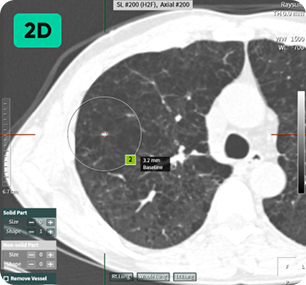

자동 결절 감지

및 폐 RADS 계산

영상 인공지능을 활용해 저선량 흉부 CT에서 놓치기 쉬운 폐 결절을 탐지하고 분석합니다.

미세 결절을 발견하면 기본 정보, 결절 개수, 크기 및 상태, RADS 범주 등 다양한 정보를 얻을 수 있습니다. 폐암으로 발전할 가능성이 있는 소견도 미리 확인하여 작업 시간을 단축하고 사례에 따라 효율적인 판독을 가능하게 합니다. 미세 결절 검출: 결절 개수, 크기, 상태, RADS 범주에 대한 포괄적인 정보 제공 잠재적 폐암 발생을 조기에 발견하여 시간 효율적인 스캔 판독을 가능하게 합니다.

작은 것부터 큰 것까지 다양한 크기의 결절 감지